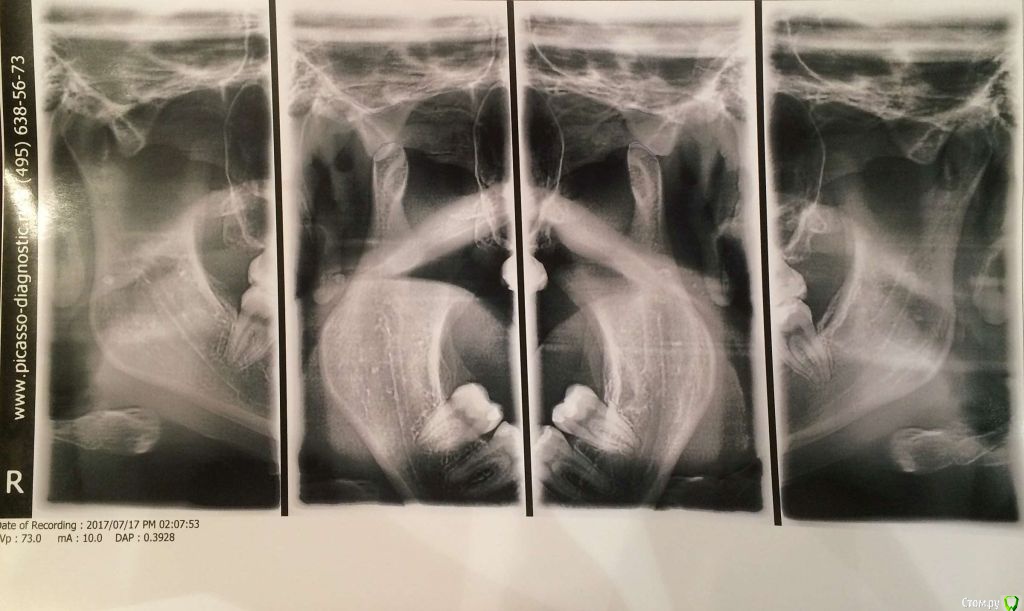

Добрый день! Очень прошу помочь с выбором врача или рекомендаций по лечению. С 2010 по 2012 год я носила брекеты (зубы были ровные, но с левой стороны верхня челюсть полностью перекрывала нижние, не было контактов, происходило стачивание). Затем с 2012 по 2016 год мне пытались исправить зубы нижней челюсти, я носила разные каппы, пластинки, то есть зубы все это время не фиксировали в определенном положении. Затем наконец в 2016-2017 году я относила полгода корректирующую каппу, которая более-менее выровняла мне нижний ряд (там была скученность). Все это время пломбы на жевательных зубах мне не меняли, они очень сильно сточились, и мне рекомендовали их заменить. Но как раз в это время у меня заболел сустав с правой стороны (на фото он соответственно слева, где и наблюдается ассиметрия). Я стала ходить по ортодонтам-ортопедам, одни говорили, что у меня все супер с прикусом, другие говорили, что клыки не под тем углом и надо снова ставить брекеты. Устав от хождений, я обратилась за диагностикой в небезызвестный центр междисдисплинарной стоматологии. Сделала там полную диагностику, по результатам которой мне предложили либо исправить брекетами клыки и поднять прикус керамическими вкладками, либо без брекетов, но тогда ставить на клыки также вкладки. Эта процедура проводится аж в три этапа и стоит как крыло самолета. Я прилагаю результаты моей диагностики. Обратилась за консультацией к другому ортопеду, который заверил, что можно обойтись временными и затем керамическими вкладками. Но помимо прикуса меня волнует ассиметрия улыбки, которая появилась в последнее время. Во-первых, я вижу невооруженным глазом, что зубы с правой стороны по высоте короче, чем с левой, то есть они меньше закрывают нижние зубы, чем с противоположной стороны, это же видно и на фото. Во-вторых, справа уголок губы при улыбке опускается как бы к низу, в отличе от левой стороны, где он идет ровно. В-третьих, с этой же правой стороны при улыбке мыщца начинается дергаться... Сейчас я уже запуталась, к какому врачу мне обращаться с данной проблемой: к ортодонту, к ортопеду, либо это гипертонус мыщц (хотя в закрытом состоянии эта ассиметрия не так заметна) Заранее благодарю за рекомендации.

Вам необходим врач-ортокраниодонт. Пытаться найти решение проблемы только на уровне зубов будет крайне трудно, да и бесполезно. Это сравнимо с симптоматическим лечением, когда идёт борьба только с симптомами заболевания, но никак не влияя на главную причину. Природа Ваших проблем (ДВНЧС, асимметрия) кроется в черепе, а точнее, в имеющимся его искажении